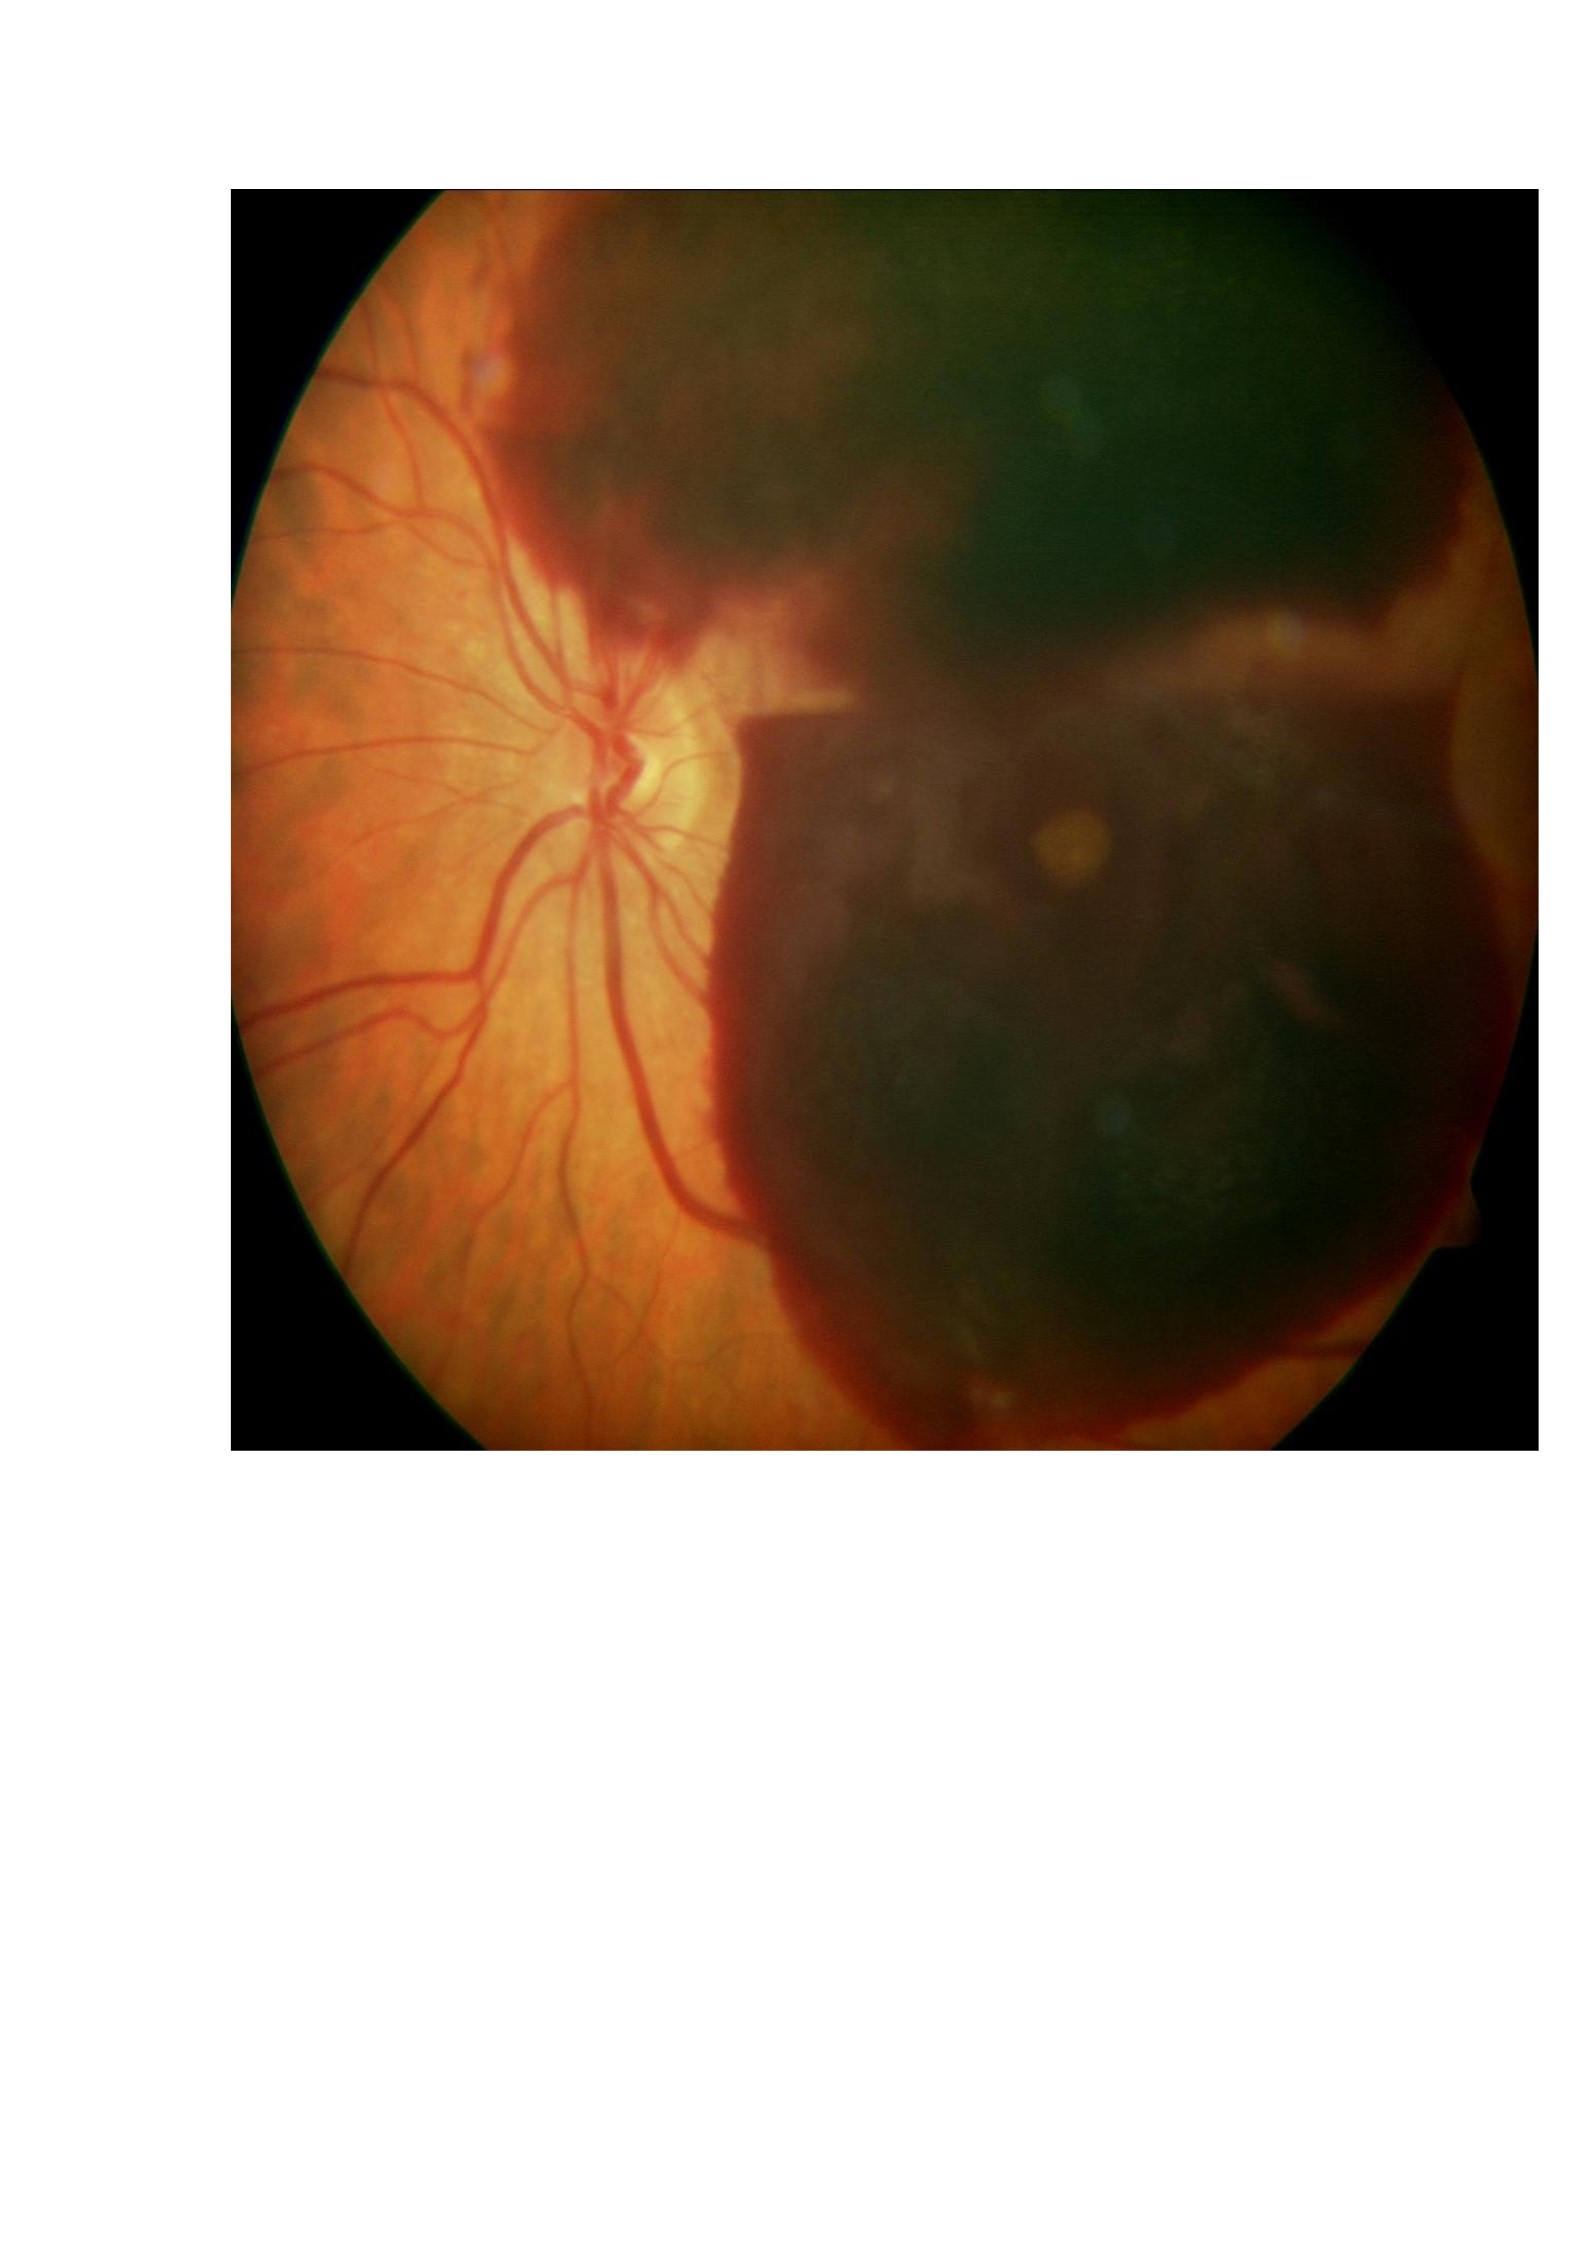

El Dr. J.S. Brown ha presentado un artículo de gran valor práctico al respecto (Retina, 2011). Comparó 2 grupos de pacientes diabéticos sometidos a vitrectomía por hemorragia vítrea, hemorragia densa premacular o desprendimiento de retina traccional.

En los pacientes de alto riesgo cardio-vascular mantuvo el tratamiento anticoagulante y en los de bajo riesgo lo suspendió. No encontró diferencias en los resultados entre ambos grupos y no se evidenció un mayor número de hemorragias vítreas postoperatorias o un mayor período de desaparición de la sangre en los pacientes que mantuvieron el tratamiento anticoagulante.